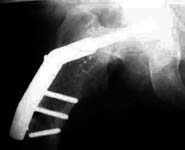

Fracture right femur isthmic region 7 years ago treated with plating. Same femur had basal fracture neck 8 months ago and this was treated with DHS - a contoured plate is seen. Now he has presented with a fracture through the upper shaft of same femur which goes thru the middle screw and has broken the last screw. Patient says he had a deformity of right femur since birth which was not corrected. Biochemically all normal values. One of my colleagues who has operated on this patient earlier said that his right femur was very vascular but histology did not reveal any specific pathology. I am not sure whether you can appreciate the following in the picture I am attaching: The DHS hip screw seems to be just getting out of the head into acetabulum. The texture of bone in the upper half appears abnormal.

My considerations: The deformity needs to be corrected if a recurrence of fracture has to be avoided. Every time he fractured the fracture has healed. The DHS hip screw cannot be retained and the present postion in the head rules out consideration for a recon type nail after deformity correction.